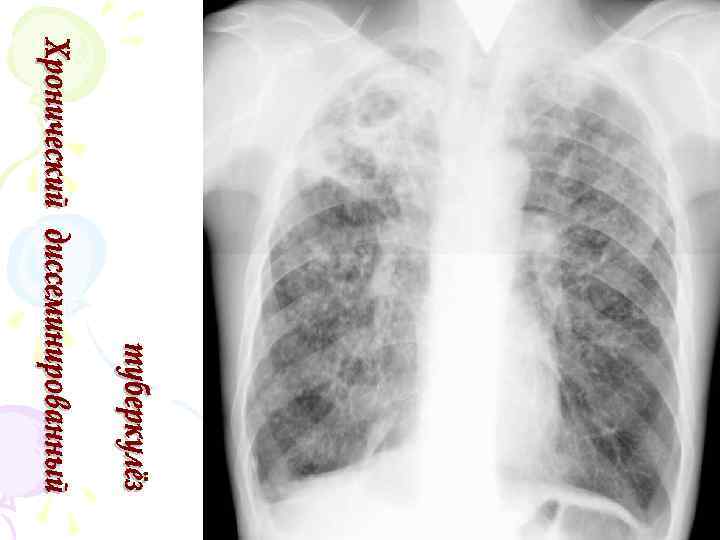

Рентгенологическая картина • Наблюдается полиморфная картина: очаги различной величины, формы и интенситвности, свежие и старые на фоне фиброзных изменений, больше в верхних отделах • Тенденции к слиянию очагов нет • Нарушается симметричность поражения • Могут наблюдаться как тонко- так и толстостенные каверны • Верхушки - интерстициальный фиброз, уменьшение объема, плевральные наложения, в нижних отделах - викарная эмфизема. С-м плакучей ивы. • Тень сердца сужена, имеет срединное положение (капельное сердце) • Фиброз и эмфизема обуславливают деформацию бронхиального дерева, что способствует развитию бронхоэктазов